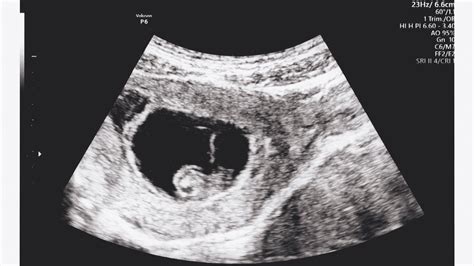

A terhesség tényét az 5. héten is ki lehet mutatni, de az embrió szívműködése a 6. héttől észlelhető. Ezért bármennyire is izgatottak vagyunk, a 6. hét után érdemes először ultrahang vizsgálatra menni, ideálisan 7-9 hét között az utolsó menseshez képest. Az ún. nulladik ultrahangvizsgálatot a terhesség megállapítására és a beágyazódás helyének tisztázására végzünk. Általában az utolsó menstruációtól számított 5. hetes terhesség már látható ultrahanggal. Ekkor egy petezsák rajzolódik ki, majd az 5. hét végére láthatóvá válik a szikhólyag és az embriócsomó is. A szívműködést inkább a 6. hét elejétől lehet kimutatni. A terhesség tényét az 5. héten is ki lehet mutatni, de az embrió szívműködése a 6. héttől észlelhető. A terhesség megállapítása, hivatalosan a terhesség ténye képi vizsgálat/ultrahang vizsgálat alapján mondható ki. A terhesség megállapítását szonográfus is elvégezheti, de hivatalos gondozásba vételt szülész-nőgyógyász szakorvos kezdeményezhet.

Mit mutat az ultrahang 4-5 hetes terhesség esetén?

A koraterhességi ultrahang vizsgálat célja a méhen belüli terhesség kimutatása. A terhességi kor függvényében a vizsgálat történhet hüvelyen vagy hason keresztül. Optimális ideje az utolsó menstruáció első napját követő 6-8. terhességi hét. A terhesség 4-5. hetében ultrahang vizsgálattal csak a petezsák mutatható ki, benne az embrió még nem látható. Ilyenkor már szépen látható a petezsák, a szikhólyag, és az embriócsomó is. A petezsákon belüli szikhólyag megjelenése már a terhesség megállapítható egyértelműen igazolva a méhen belüli terhességet. A 6. héttől már a petezsákban legtöbbször látható már az embrió és szívműködése is észrevehető vagy hallható. Nem marad tehát le semmiről az, aki biztosra megy és csak a terhesség 6. hetét követően megy ultrahangra. A terhesség tényét az 5. héten is ki lehet mutatni, de az embrió szívműködése a 6. héttől észlelhető.

A szonográfus szakszavaival: A vizsgálat célja a méhen belüli terhesség kimutatása. A terhességi kor függvényében a vizsgálat történhet hüvelyen vagy hason keresztül. Optimális ideje az utolsó menstruáció első napját követő 6-8. terhességi hét. A koraterhességi ultrahangvizsgálat során megítélhetjük a petezsák elhelyezkedését, alakját, mérhetjük átmérőjét, a szikhólyag méretét és az embrió fejtető-farok távolságát (CRL), valamint áttekinthetjük a környező kismedencei területeket.